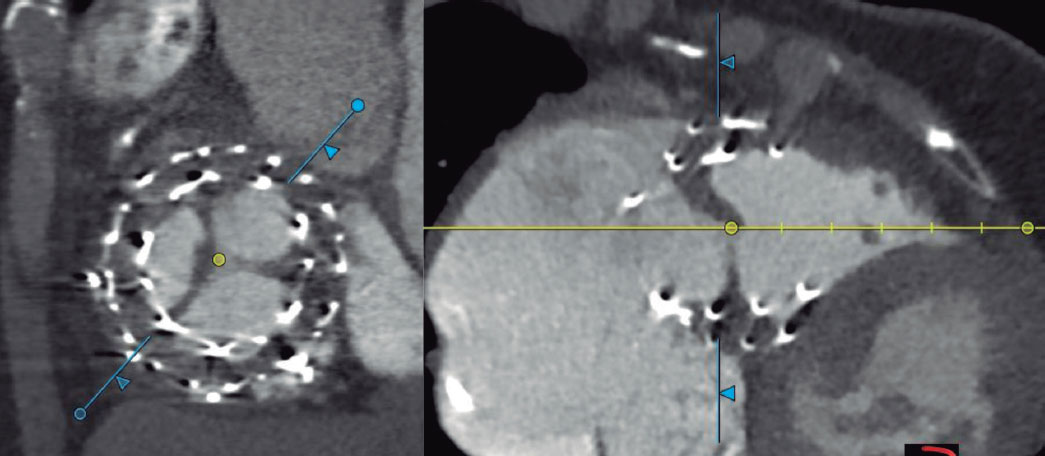

When a CN is suspected on coronary angiography, intracoronary imaging—preferably OCT, with IVUS as an alternative—will be performed to confirm the diagnosis. After confirmation of a CN in the target lesion, patients will be randomized on a 1:1 ratio to receive a DEB or a DES. Randomization will be stratified to ensure a balanced distribution of eruptive and non-eruptive nodules across both treatment groups. A CN (figure 2) will be defined as a calcified segment with an accumulation of protruding nodular calcification (small calcium deposits) with disruption of the fibrous cap (eruptive CN) or an intact thick fibrous cap (non-eruptive CN).28-30

Figure 2. Calcified nodule appearance on angiography (A), optical coherence tomography (eruptive [B] and non-eruptive [C]) and intravascular ultrasound (D).

Intracoronary imaging with either OCT or IVUS (the same imaging modality that was initially used) is recommended at the end of the procedure.